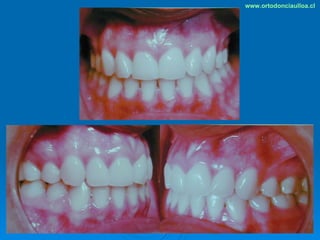

Este documento presenta dos casos clínicos de pacientes que recibieron tratamiento de ortodoncia. El primer caso fue de una paciente femenina de 14 años con apiñamiento dental y mordida cruzada que fue tratada mediante extracción de premolares y alineamiento dental. El segundo caso fue de un paciente masculino de 14 años con clase II esqueletal y desarmonía dentomaxilar que fue tratado con extracción de premolares y corrección de mordida. Ambos casos mostraron mejoría después de 3 años de tratamiento.